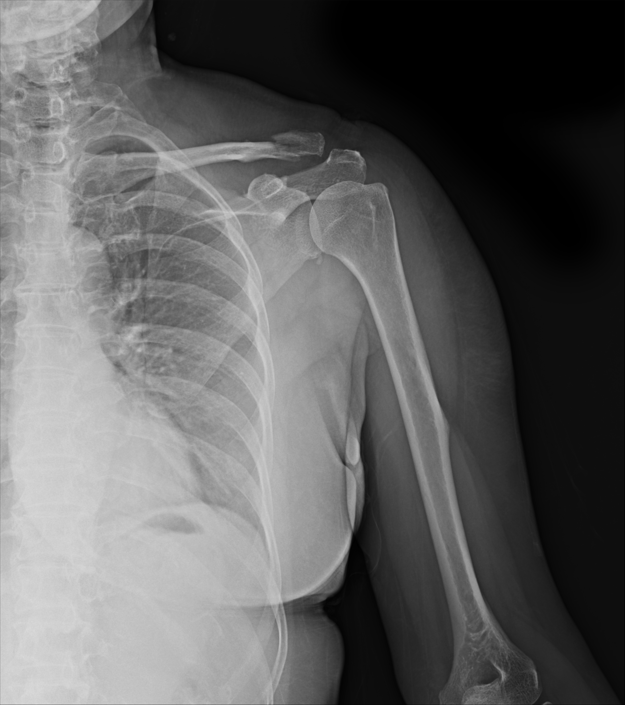

회전근개파열

회전근개파열은 어깨의 회전근개(어깨를 안정화하는 근육군)가 찢어져 어깨 통증과 기능 장애를 유발하는 상태입니다.

회전근개파열은 적절한 치료를 받지 않으면 만성 통증과 기능 저하를 초래할 수 있으며, 장기적으로는 어깨의 근육 위축과 관절의 비정상적인 움직임이 발생할 수 있습니다.

심각한 경우 수술이 필요할 수 있으며, 조기 치료를 하지 않으면 회복이 지연될 수 있습니다.

회전근개파열은 어깨의 회전근개를 구성하는 근육이나 힘줄이 부분적 또는 완전히 파열된 상태로, 보통 과도한 사용이나 외상으로 발생합니다. 이로 인해 어깨의 움직임과 기능에 심각한 제한이 생깁니다.